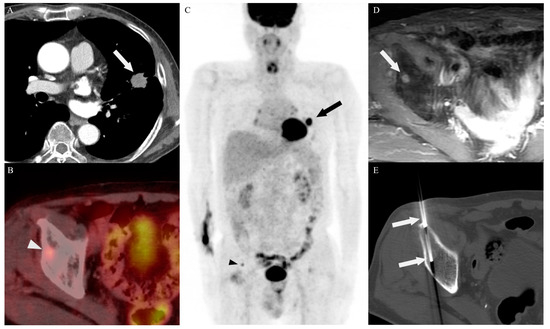

3.2. Biopsy Characteristics and Outcomes

3.4. Target Site Selection, Complications, and Diagnostic Yield According to PET/CT Timing